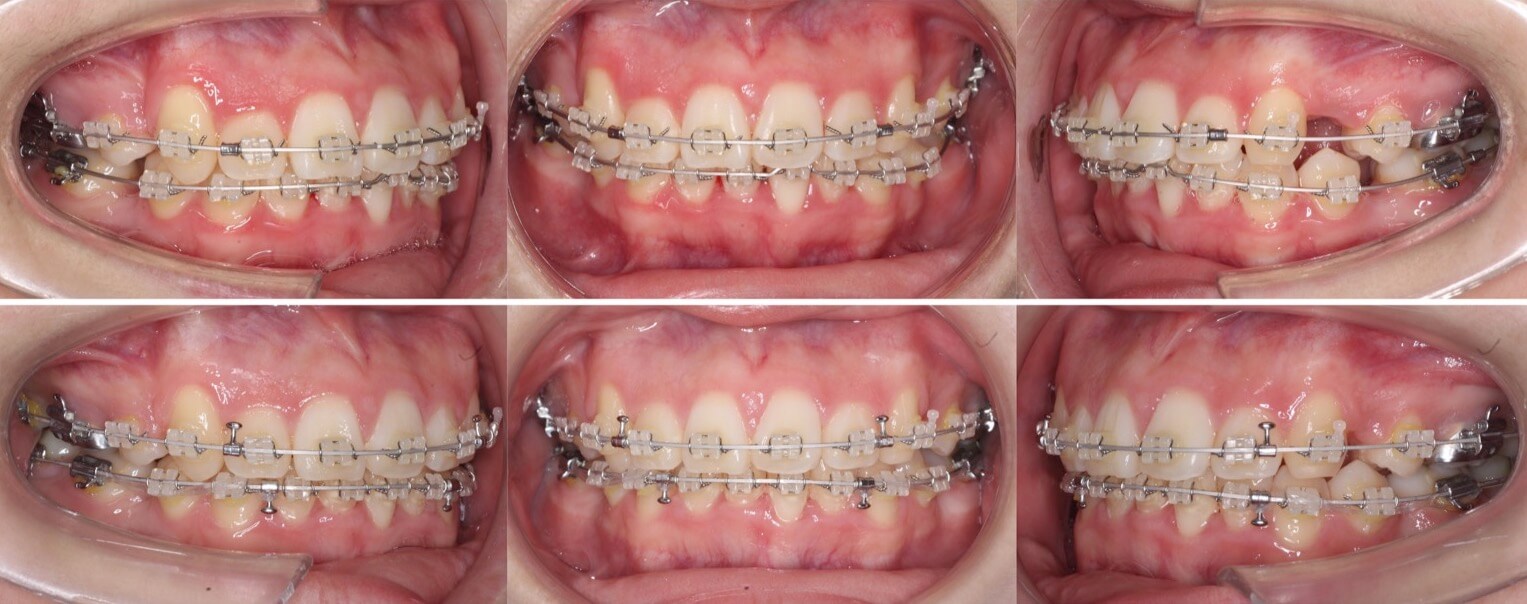

高校生女性・中程度叢生・唇側矯正装置・抜歯

八重歯と上下の正中線の不一致があるケースです。左右の抜歯部位を変えたり、下の歯並びをIPRも併用して顎間ゴムで回転させることで正中線を上下の正中線を一致させました。骨格に大きな非対称がなかったため上手くいったケースになります。

<症例概要> 難易度★★★☆☆

主訴:でこぼこ

年齢・性別:高校生女子

住まい:千葉県八千代市

症状:叢生・正中線不一致

治療方針:抜歯空隙閉鎖・右下後方移動・IPR

抜歯:右上第二小臼歯・左上第一小臼歯

治療装置:唇側矯正装置

治療期間:1年11か月

リテーナー:上下プレートタイプ+フィックスタイプ

治療費用:968,000(税込)

代表的副作用:痛み・治療後の後戻り・歯根吸収・歯髄壊死・歯肉退縮

▶︎その他の副作用